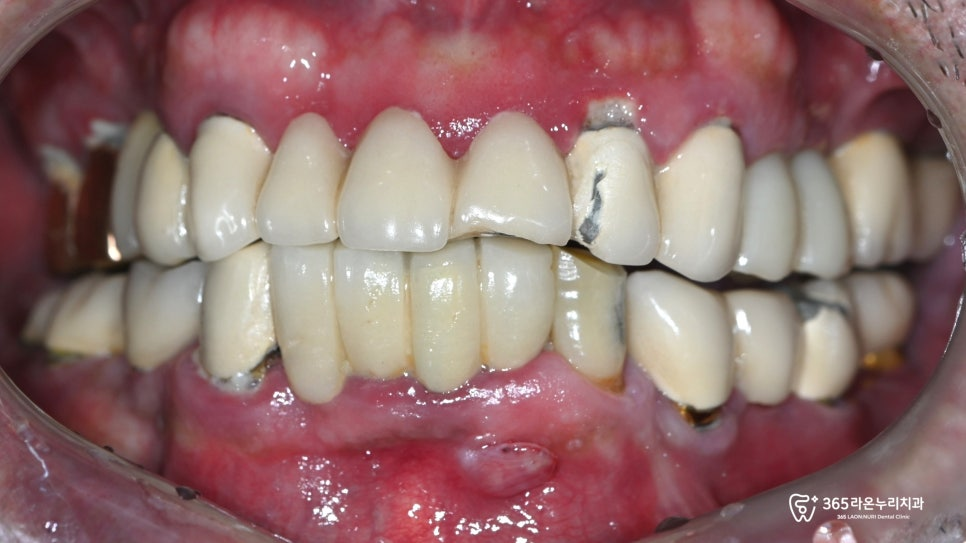

특히 이미 임플란트나 보철치료 등

다양한 치료 이력이 있는

60대 이상 고령 환자분들의 경우,

정기검진의 중요성은 더욱 강조됩니다.

이는 치근우식, 이차우식, 치근단 병소와 같은

복합적인 구강 질환들이 기존 치료 부위와 상호작용하며

더 복잡한 양상으로 진행될 수 있기 때문입니다.